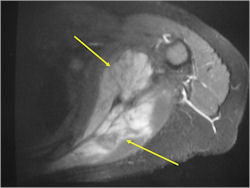

- Soft Tissue Mass in 90% of of cases

- Ewing sarcoma is one of the most aggressive tumors

- High propensity for Local recurrences

- Distant metastases (predominantly in lungs and other bones)

- Lesions grossly confined to bone have a better prognosis than those with a soft tissue component

- Tumors greater than 8cm in maximum dimension and those with greater than a volume of 100cc have been associated with a worse prognosis